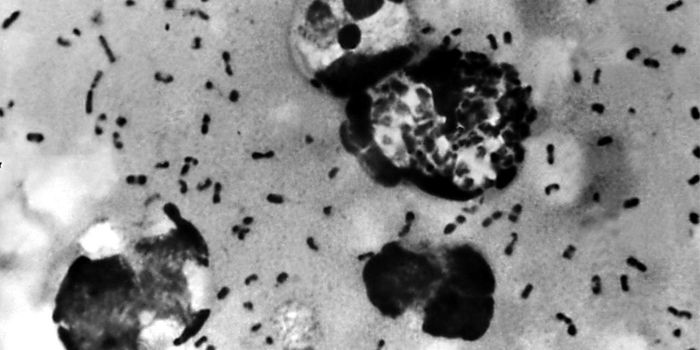

SEP 19, 2016ImmunologyYersinia pestis, the bacterial species responsible for numerous and deadly outbreaks of plague throughout human history, ...